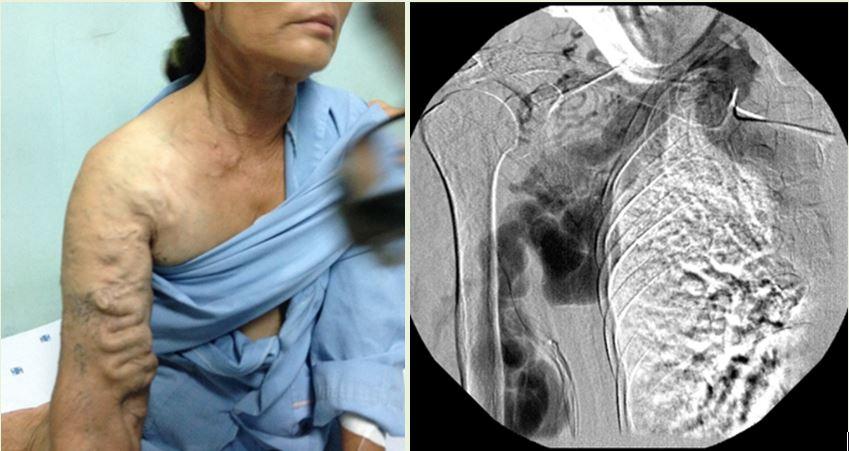

Nữ cựu chiến binh bất chấp nguy cơ tử vong để bác sĩ làm tắc mạch mạch máu giãn nở tới 3cm

Một nữ cựu chiến binh 60 tuổi, có vết thương từ 40 năm trước do đạn trúng vùng thượng đòn phải. Sau khi lành thương, bà vẫn có cảm giác mạch máu vùng vai ngày càng giãn to theo thời gian, nghe có mạch đập “phà phà”, “ào ào”.

Nữ cựu chiến binh đã đi khám bệnh nhiều nơi vì mệt, siêu âm có giãn buồng tim, suy tim… Sau khi thăm khám tại các bệnh viện hàng đầu, hội chẩn nhiều chuyên khoa và với giáo sư nước ngoài… các chuyên gia đều nhận định là không thể phẫu thuật. Lý do là tĩnh mạch bao phủ cả vùng vai, đập dữ dội, nếu phẫu thuật bộc lộ ra cũng khó lòng tiếp cận được vị trí cần xử lý. Về nguyên lý đây cũng là một trường hợp thông động tĩnh mạch với lưu lượng lớn, BS Cường nhận thấy cần gây tắc tại điểm cuối cùng của động mạch và điểm đầu tiên của tĩnh mạch thì mới hiệu quả, tránh mạch máu bàng hệ tăng sinh. BS Cường vận dụng hết tất cả dụng cụ hiện có cho ca can thiệp khó khăn này, để chặn được động mạch dưới đòn lúc này đã giãn hơn 3cm, tiến hành đặt bóng và bơm keo (nếu đặt coil bệnh nhân sẽ tốn hơn 2 tỷ và coil có thể trôi về phổi, bệnh nhân sẽ tử vong). Rất may mắn, ca can thiệp đã thành công.

DSA can thiệp

Sau gây tắc

Trước đó, bệnh nhân đã phải ký cam kết có thể tử vong trên bàn mổ, BS Cường cũng chưa từng gặp trường hợp tương tự. Tuy nhiên nữ cựu chiến binh vẫn nhất quyết can thiệp: “Tôi là thương binh, nếu tôi tử vong thì là liệt sĩ thôi, không sao cả!”.